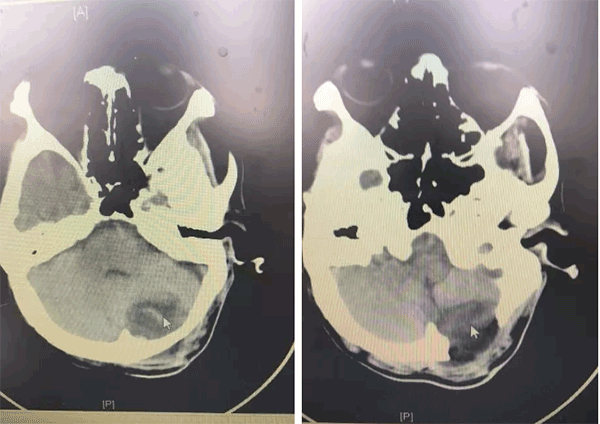

出院前复查颅脑胸部CT示积液和肺不张胸腔积液恢复良好,患者可以正常行走,现已经顺利出院。